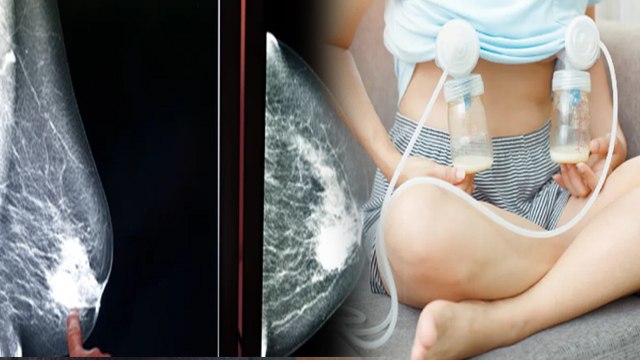

From Breastfeeding To Breast Cancer: All you need to know | ब्रेस्टफीडिंग | वनइंडिया हिंदी | *News

बच्चा (Child) जब दुनिया (World) में आता है, तो सबसे पहली चीज जो वो ढूंढता है, वो है मां का दूध. लेकिन इतने छोटे से बच्चे को पता कैसे चलता है कि दूध कहां से मिलेगा? #OIDW #OneIndiaDW #SehatTalk DW Hindi, DW Hindi Sehat Talk, Sehat Talk Isha Bhatia Sanan, DW Hindi Isha Bhatia Sanan, breastfeeding, breastfeeding vlogs, breast cancer, breast cancer symptoms, breast cancer awareness, breast cancer symptoms in urdu, breast cancer symptoms in hindi, tahira kashyap breast milk, breast milk storage, breast implants and cancer, ब्रेस्ट फीडिंग मशीन, बच्चे को दूध कब तक पिलाना चाहिए, ब्रेस्ट कैंसर से बचने के उपाय, मां का दूध कैसे पीते हैं बच्चे, मां का दूध बढ़ाने के उपाय,oneindia hindi,oneindia hindi news,वनइंडिया हिंदी, वनइंडिया न्यूज, वनइंडिया हिंदी न्यूज़